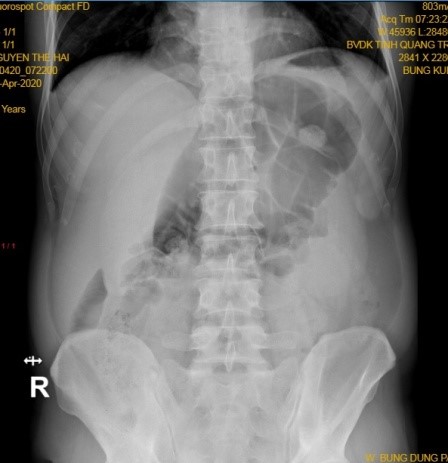

Tại khoa nội tổng hợp bênh nhân tiếp tục được điều trị theo hướng viêm dạ dày cấp với kháng sinh truyền tĩnh mạch, kháng tiết và băng niêm mạc dạ dày tuy nhiên tình trạng bệnh không cải thiện với đau tức liên tục vùng thượng vị , nôn khan, bụng chướng, ghi nhận hố chậu phải mềm. Tiêm Morphin bệnh nhân cũng không dịu đau. 6h ngày 25/4/2020 thăm khám ghi nhận: bệnh nhân không sốt, đau tức thượng vị và quanh rốn, hố chậu phải không đau, nôn khan nhiều, bụng chướng, chưa trung và đại tiện. Bệnh nhân được xử trí đặt thông dạ dày, truyền dịch, chống có thắt, thụt tháo phân. chụp Xquang bụng đứng thấy hình ảnh quai ruột non giữa ổ bụng chướng hơi lớn, không có liềm hơi dưới cơ hoành, không có mức hơi dịch điển hình (Hình 1). Siêu âm bụng lần 2: kết quả: gan nhiễm mỡ, dịch ổ bụng âm tính, làm lại xét nghiệm máu ghi nhận BC 15 G/l, BCĐNTT 83%, Crp 123. Bàn giao tua sau theo dõi tiếp

Xquang bung dung sang

Hình 1. Xquang bụng đứng sáng 25.4.2020